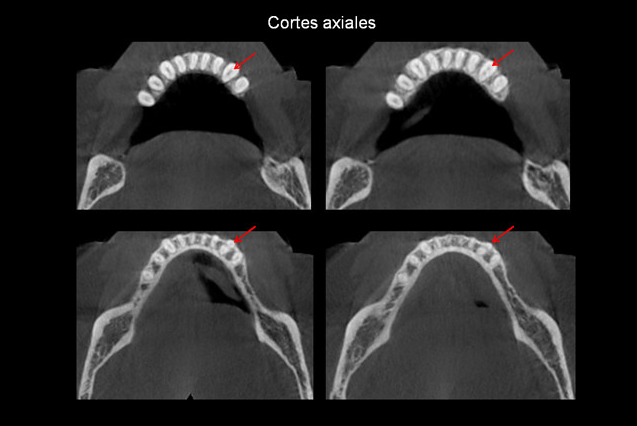

Paciente femenino de 54 años de edad, asintomática, es referida a la consulta para la evaluación con Tomografía volumétrica previa a la colocación de implantes. A la observación de los cortes axiales se evidencian dos raíces en la pieza 3.3, el corte transaxial muestra la bifurcación a nivel del tercio cervical.

El canino inferior tiene una raíz y un conducto excepto en el 4.5- 22% que tiene dos raíces, una vestibular y una lingual cada una con un conducto. La bifurcación se observa en la mayoría de casos hacia el tercio apical. Se han presentado variaciones de dos raíces con tres conductos pero con poca frecuencia.